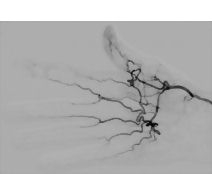

Digital Subtraction Angiography (DSA) of Arteries of Hand